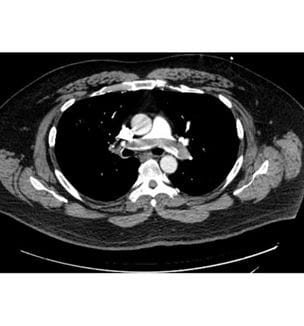

Experience at University Hospitals Cleveland Medical Center Shows Effectiveness of Pulmonary Embolism Response Team Approach

PERT members also launching clinical trials of new interventional devices, studying use - Innovations in Pulmonology & Sleep Medicine